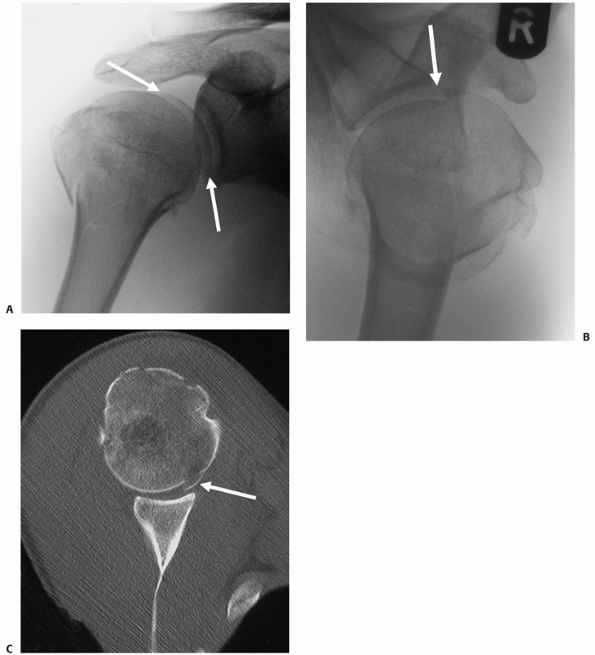

![]() |

FIGURE 35-17 A. “Double-shadow” on the anteroposterior radiograph (arrow) is pathognomic of a head-split fracture. The split is also seen on the modified axial view (B) but the extent of head involvement is best assessed using a computed tomography scan (C). The white arrows show the head-split.